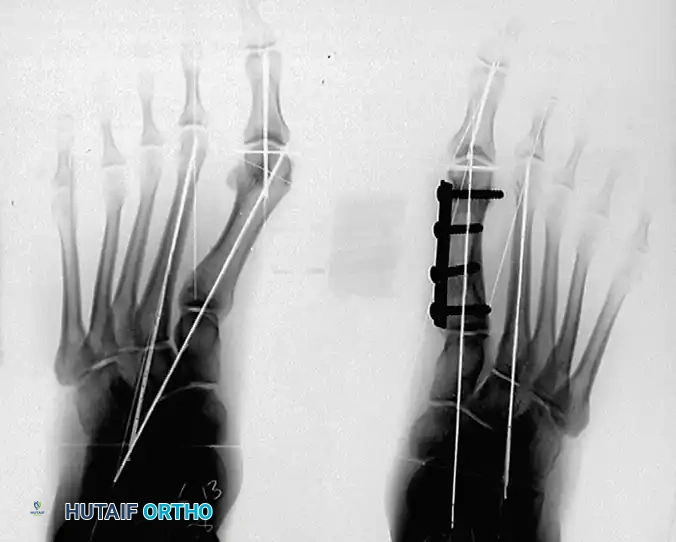

7. Internal Fixation

Rigid internal fixation is paramount to maintain the complex bi-level correction.

- Select a four-hole small fragment tubular plate, or a five- to six-hole mini tubular plate, depending on the patient's anatomy. The plate size is strictly dictated by the space available between the proximal physis and the distal metatarsal articular surface.

- Apply the plate medially. Insert the first 3.5-mm screw into the most proximal hole, loosely fixing the plate to the metatarsal base.

- Ensure the distal hole of the plate fits perfectly over the remaining metatarsal head.

- Place the distal screws through the plate, directly across the osteoperiosteal flap, and into the metatarsal head.

- Place the remaining central screws. Utilize eccentric drilling if necessary to achieve inboard compression across both the proximal and distal osteotomy sites.